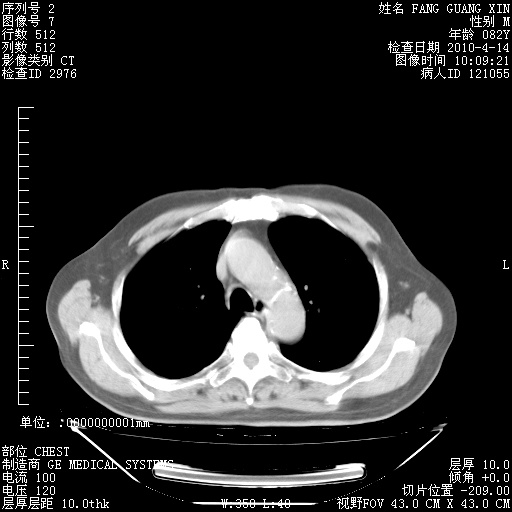

4月14日肺部CT

23.JPG

24.JPG

25.JPG

26.JPG

肺部CT平扫未见异常。